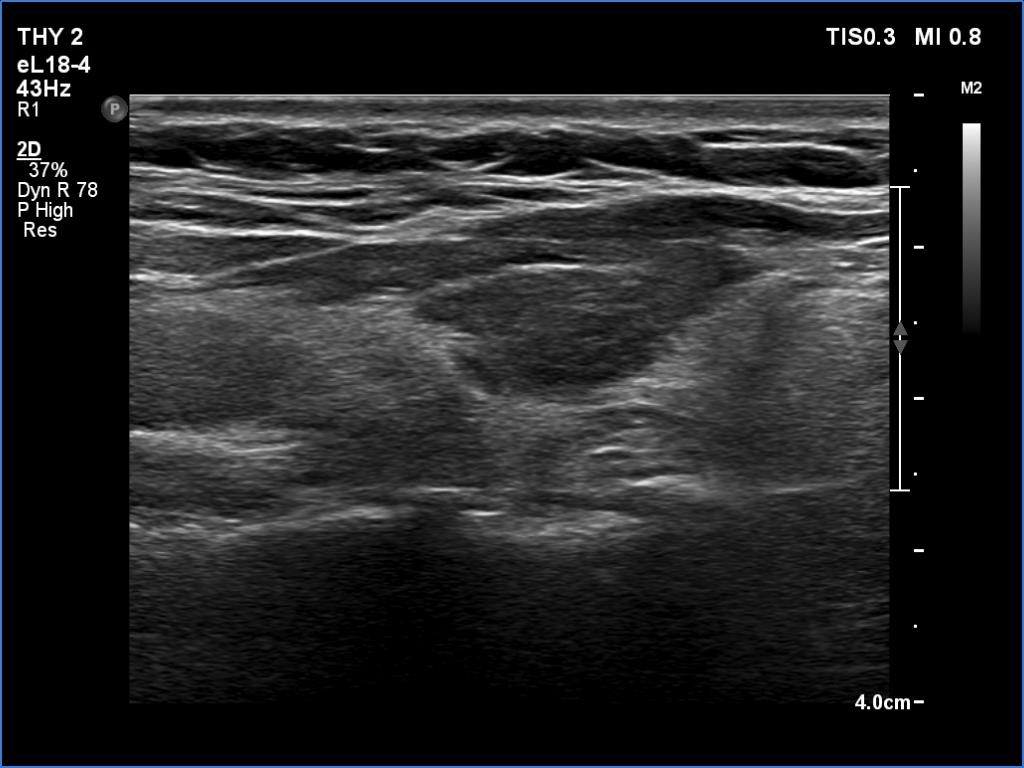

Ultrasonography. The thyroid was atrophic. Both lobes were composed of a central, larger hypoechoic area surrounded with echonormal tissue. The pattern did not correspond to nodule. The vascularity was decreased.

Comment. A central hypoechoic part surrounded with echonormal tissue is one of the typical presentations of Hashimoto's thyroiditis, not infrequently misinterpreted as a large hypoechoic nodule which occupies great part of a lobe. The irregular margins, the infiltrative borders of the thyroiditis are the main clues of differentiation this presentation from nodular goiter. The pattern can be observed usually in both lobes which is also characteristic of this form of thyroiditis.